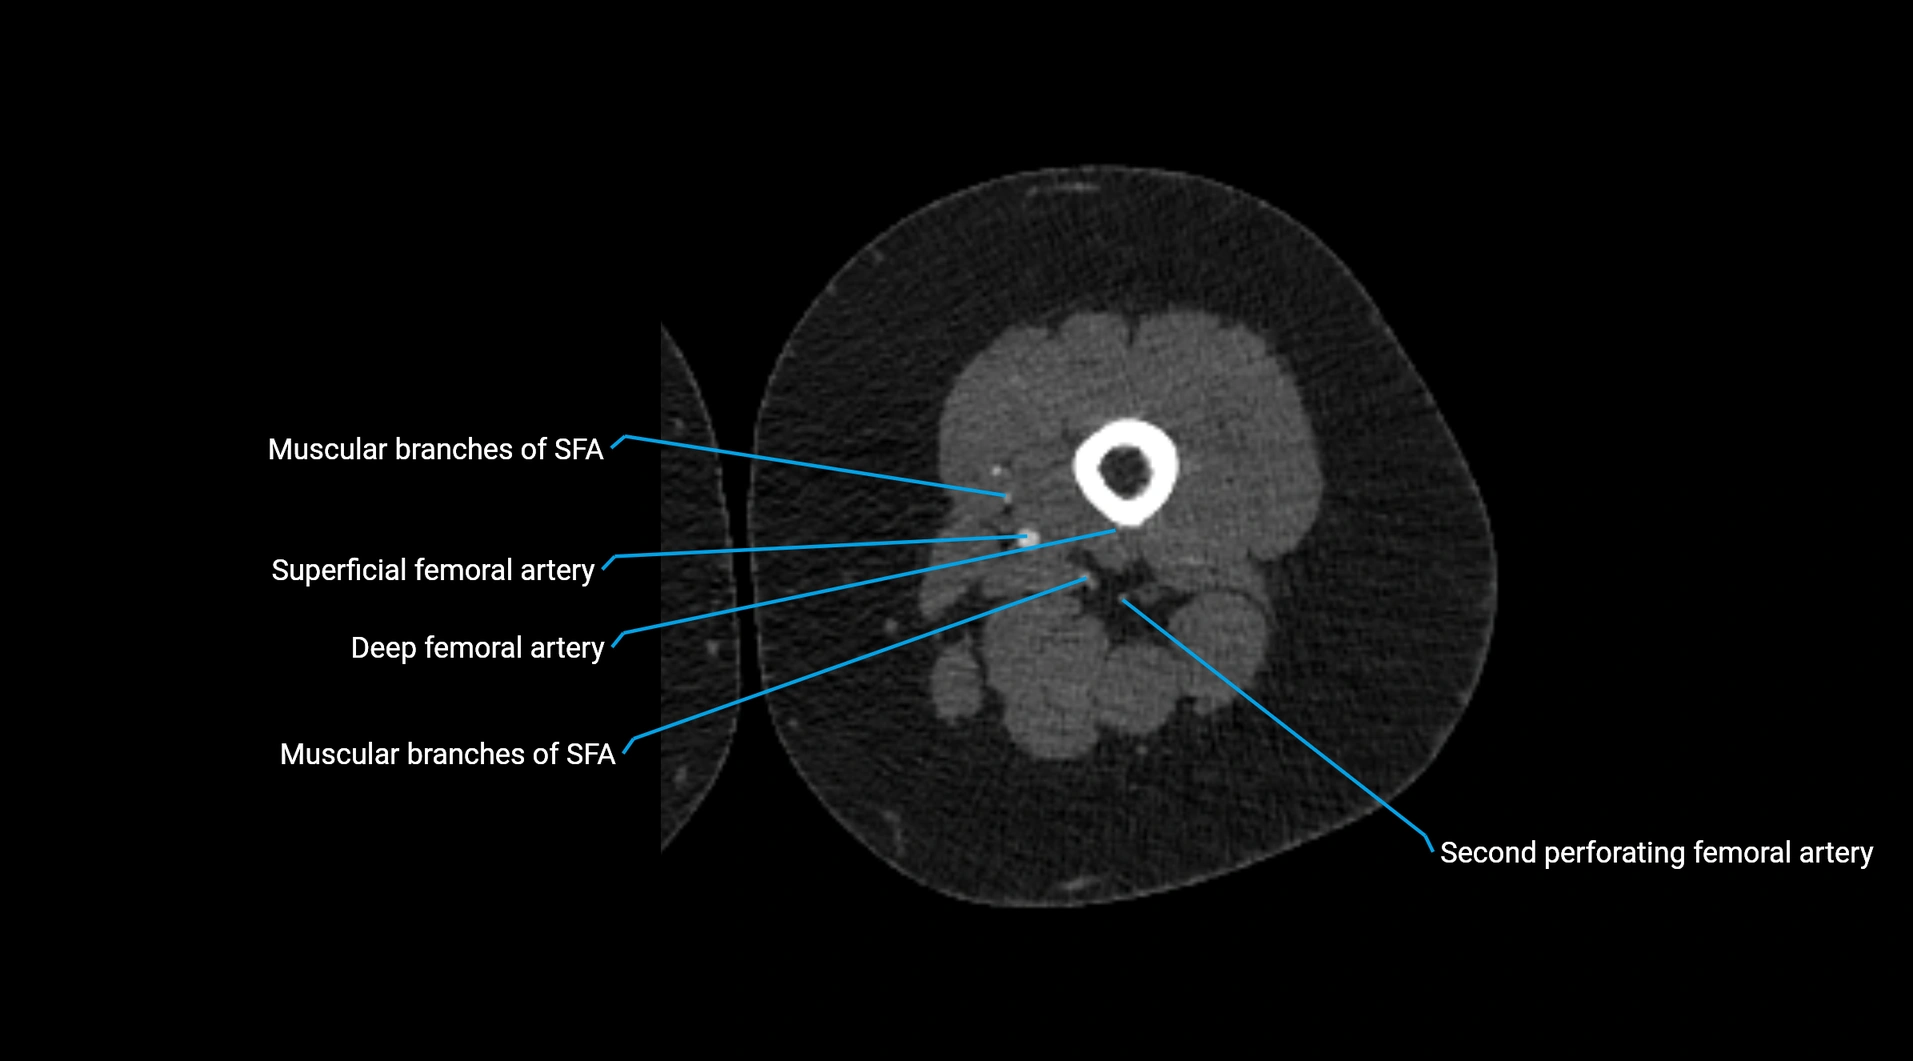

CT images

image

Contrast-enhanced CT (CTA):

• Gold standard for abdominal aortic imaging

• Provides excellent detail of lumen, wall, aneurysm, thrombus, and branch vessels

• Multiplanar and 3D reconstructions help in aneurysm measurement, stent graft planning, and dissection evaluation